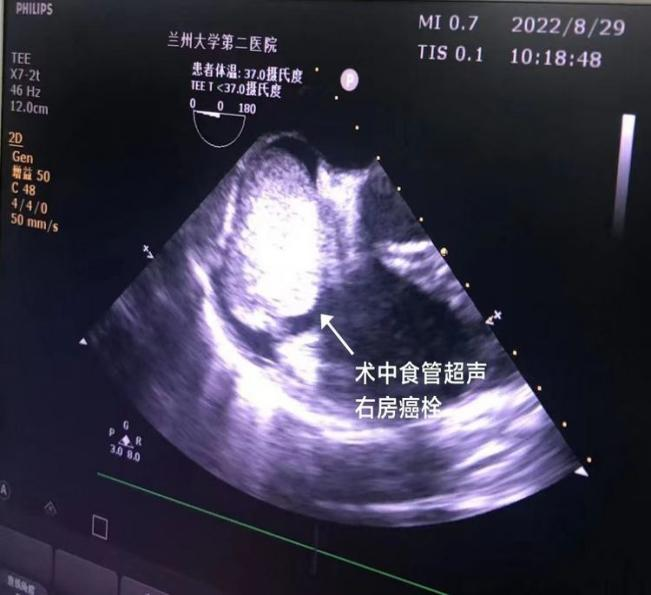

鉴于患者病情罕见复杂、手术难度大、风险高,兰大二院充分发挥多学科讨论(MDT)优势,积极组织包括麻醉科、心胸外科、血管外科、普外科、心内科、超声科、影像科等相关科室进行术前多学科讨论,群策群力,对手术方案和手术分险进行了讨论和总结。最终在经过详细周密的术前准备后,泌尿外科二病区与普外科、心外科及麻醉科通力合作,密切配合对患者实施了右肾根治性切除术+肝脏翻转术+胆囊切除术+体外循环下右心房切开取栓术+腔静脉瘤栓切除并腔静脉血管成形术,在术中食道超声的动态监测下成功切除右肾肿瘤并完整切除瘤栓,手术时长约8小时,瘤栓长约30cm, 手术顺利, 术后经过一周的精心护理后,患者痊愈康复出院。